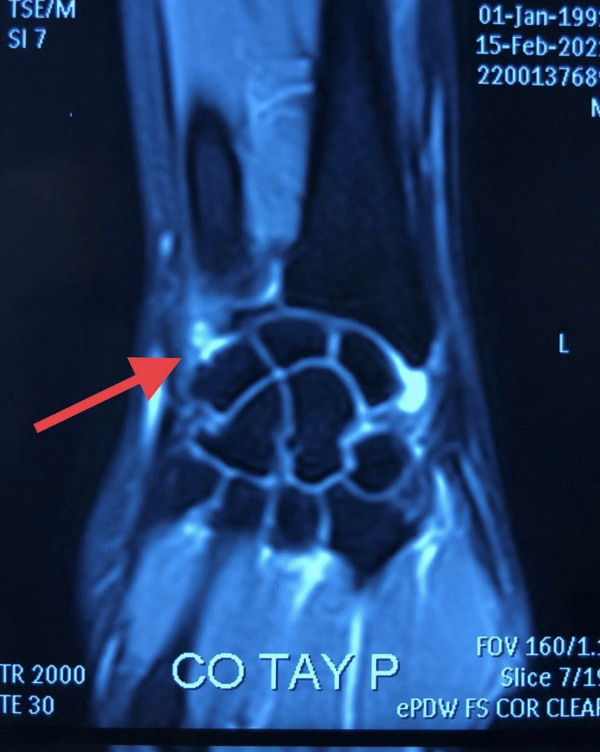

![]() |

Hình ảnh tổn thương phức hợp dây chằng sụn sợi tam giác TFCC trên phim MRI (Ảnh - BVCC) |

Đồng thời, cùng với việc chẩn đoán trên lâm sàng thì chẩn đoán hình ảnh cũng rất quan trọng, với phim Xquang thông thường khó phát hiện bệnh, cần dựa vào các kỹ thuật chẩn đoán hình ảnh chuyên sâu, ví dụ như phim chụp cắt lớp hoặc cộng hưởng từ.

Đặc biệt cộng hưởng từ có giá trị cao trong việc đánh giá, phát hiện cũng như định hướng các tổn thương, nhất là các tổn thương dây chằng ở cổ tay. Bác sĩ chuyên khoa chẩn đoán hình ảnh cũng phải được đào tạo bài bản mới có thể phát hiện được các tổn thương. Khớp cổ tay rất nhỏ, đòi hỏi các động tác tinh tế cũng như các trang thiết bị đặc thù, chuyên sâu như ống nội soi, camera, các dụng cụ kèm theo hỗ trợ.